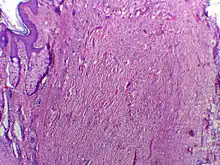

Micrographie de chéloïde. Les fibres épaisses de collagène sont caractéristiques de ce processus de cicatrisation aberrante. Coloration à l’hématoxyline et à l’éosine.

Le processus de cicatrisation est caractérisé par un équilibre entre la synthèse et l’hydrolyse du collagène. Pendant la phase de prolifération, le taux d’apport en collagène dépasse celui de sa lyse. Puis apport et lyse s’équilibrent au cours de la phase de maturation. À cette étape, le collagène structurel de la cicatrice formée est réorganisé par l’action conjointe de la lyse et de la synthèse, aboutissant à une cicatrice mature.

Dans le cas des cicatrices chéloïdes et hypertrophiques, le point d’équilibre, généralement atteint 3 à 4 semaines après la blessure, n’est jamais atteint. L’apport de collagène reste supérieur à sa lyse pour une période indéfinie, provoquant une boursouflure au niveau de la cicatrice[1].